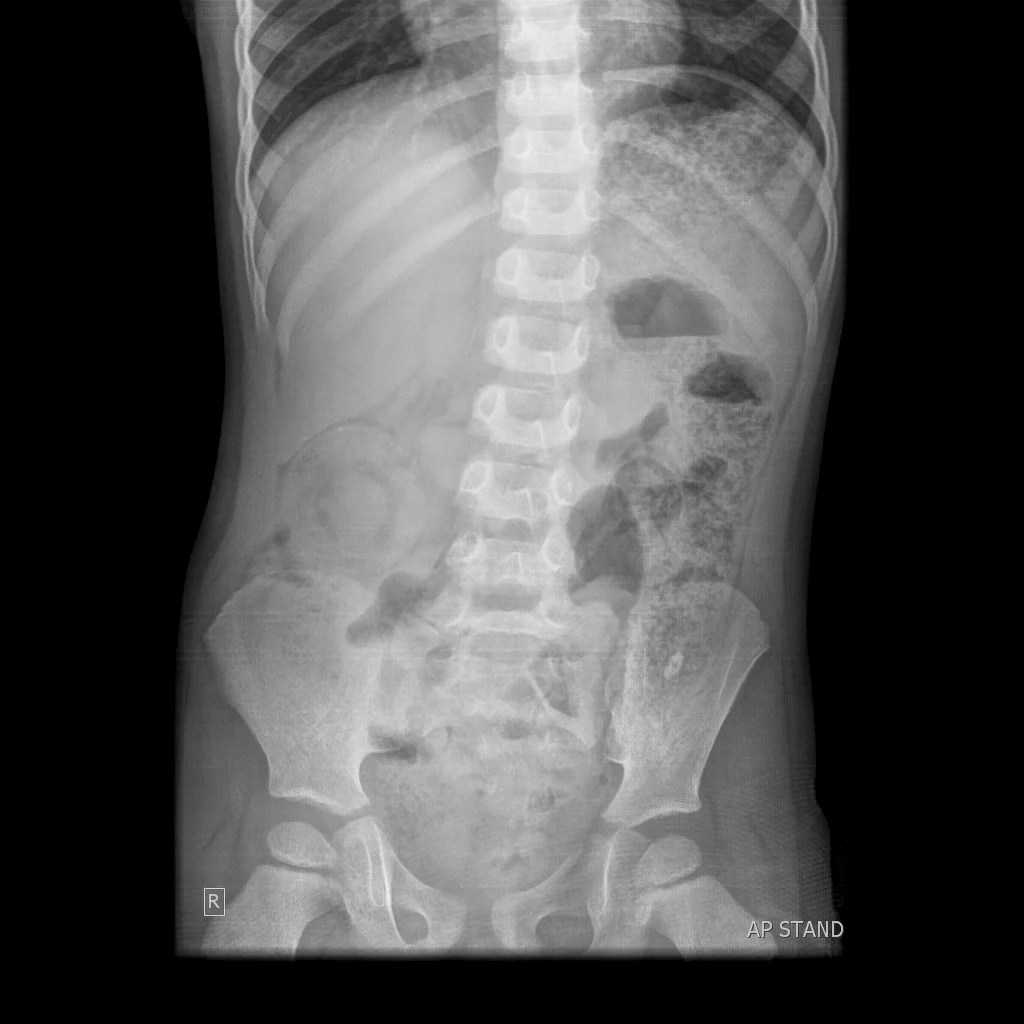

Plain abdominal Xray in erect position showing multiple airfluid